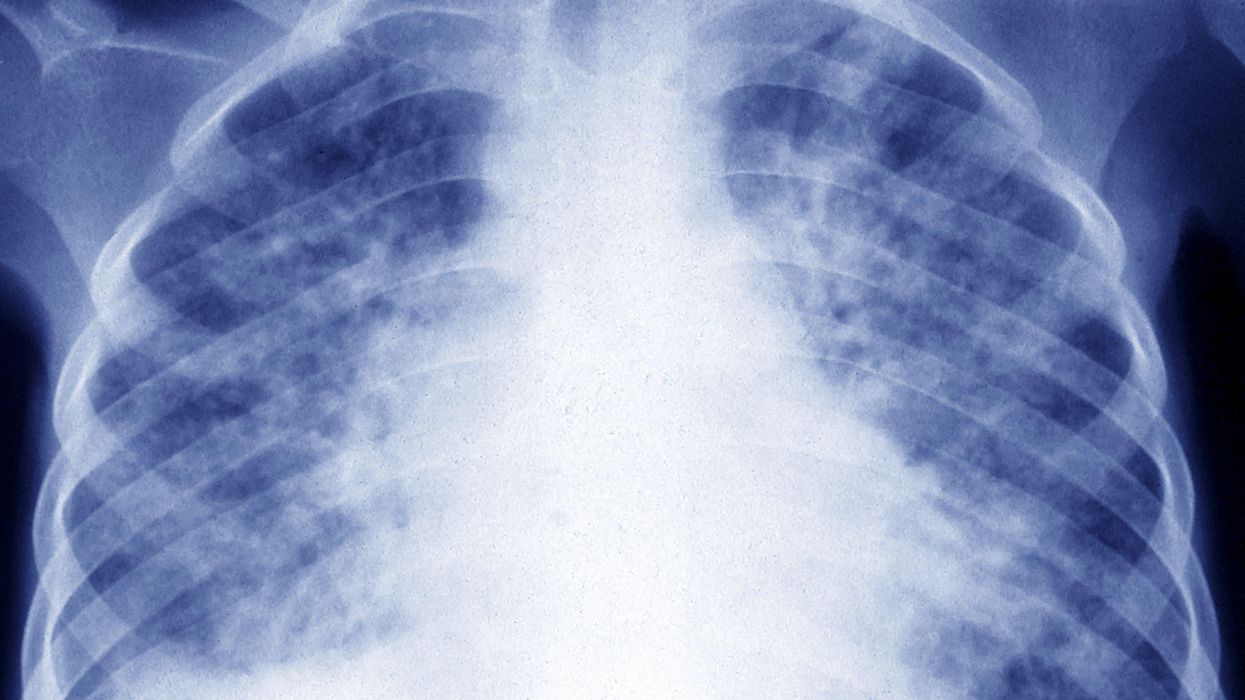

Photo By BSIP/Universal Images Group via Getty Images

When she refused to receive an informal, over-the-phone diagnosis and pushed for an X-ray, her fears were confirmed: She had a cancerous mass inside her chest, measuring approximately four inches. She was soon diagnosed with Hodgkin's lymphoma.